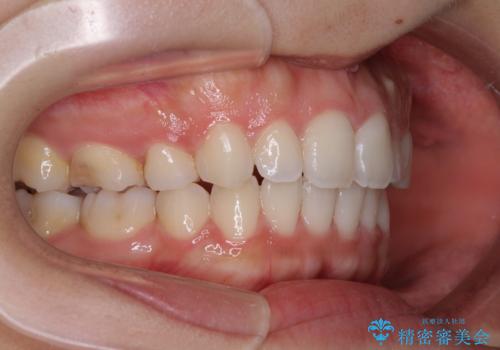

- 審美装置

- 2年2ヶ月

上顎抜歯のみでは奥歯の咬み合わせを改善することが困難であったため、途中で下顎小臼歯も抜歯をしました。

抜歯のタイミングが遅れると治療期間が長期化するため、速やかに抜歯の判断をし、2年強の期間で治療を終えることができました。